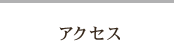

院内に設置された歯科用CTで確実な検査を行います

院内に設置された歯科用CTで確実な検査を行います- 歯科に特化したCTスキャンを導入し、患者様の患部の状態を3次元画像で正確に把握できる環境を整えています。従来の歯科治療では経験と勘に頼らざるを得なかったインプラントなどの精密治療でも安全に行うことができます。